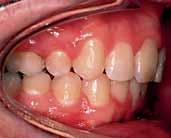

The oral hygiene was fair but needed improvement prior to orthodontic treatment. All teeth from the left permanent second molar to the right have erupted in both the upper and lower arches. The patient had carious lesions in both upper first molars, upper left second molar and lower left first molar. The maxillary arch was spaced with a midline diastema. Furthermore, there was mild lower labial segment crowding (4mm). The incisor relationship was Class II division 1, the overjet was 12 mm whereas the overbite was increased and complete to the palate

and causing trauma to the palatal mucosa. The centrelines were coincident and the buccal segment relationship was 1/2 unit Class II on both sides (Figure 2).

The treatment of the case was planned in stages. Stage one consistedof improving the oral hygiene of the patient and management of all carious lesions and assesses the compliance and attitude of the patient towards orthodontic treatment. The next stage involved the reduction of the overbite. The patient presented with a deep overbite that was causing damage to the palatal mucosa (Figure 2). This was achieved with an anterior bite plane removable appliance and bonding of the lower arch. This appliance will free the occlusion of the buccal segment teeth and if worn consistently, will “passively” limit further eruption of the incisors but allow the lower premolars to erupt, thus reduce the increased overbite (Figure 5).